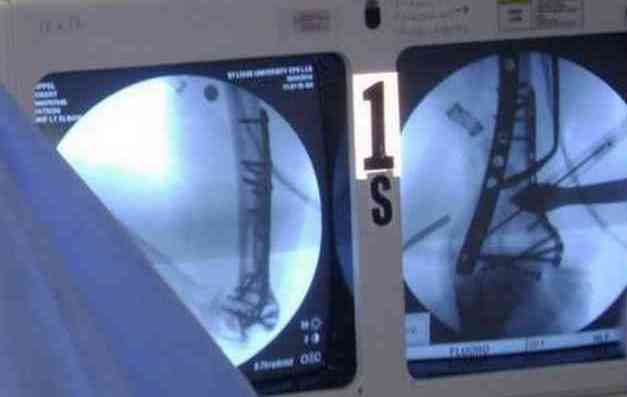

Впечатления об американской ортопедии. По проторенной коллегами дорожке в апреле по приглашению доктора Кульджанова Д., мы, 2 врача из казахстанской провинции -Канат Тезекбаев и Чертковер Григорий \ака Антон Андрианов\ провели 2 недели в университетской клинике города СентЛуис, Миссури. В прошлом году Никита Заднепровский, ранее побывав там, писал на форуме свои впечатления. Не желая повторяться, хочется довести до сведения коллег малую часть того, что нас поразило в США. Хотя одному из нас довелось поучиться три месяца в ФРГ по гранту АОАА и видеть клиники Швейцарии увиденное было ошеломляющим. Во-первых, подготовка врачей ортопедов длится 5-6 лет после колледжа, рабочая неделя их длится до 80 часов в неделю .Они –резиденты, закрывают все дежурства, прием пациентов. Опытные их учителя вызываются в ночное время по графику и очень многое резиденты делают сами под их контролем. Через пять лет к 33-35 годам он выходит самостоятельными врачами и ищут себе высокооплачиваемое место работы. Все стационары и амбулаторные приемы, частные или управляются частными компаниями, вся хирургическая служба высокодоходна и с врачами очень считаются, особенно по части приобретения заказанной ими техники. Экономическая целесообразность оставляет врачу только труд его квалификации, выписки, например, он диктует по телефону, мылом они летят в Индию, где дешевле труд машинистки, а к утру они уже в печатном виде у него в компьютере. Библиотека департамента ортопедии заставила утереть слезы доброй зависти, как и стопки журналов со всего мира на столе у профессора Кульджанова. Отсутствуют пленки рентгенограмм, доступ к сети с любого ПК, где хранятся все исследования пациента от поступления до амбулаторного этапа, интернет -до операционной. Удивительно крепок их командный дух, все дружно радуются быстро и удачно сделанной операции, бегут смотреть, что творится у коллеги, могут помыться на короткий момент для помощи и изучения, после идти продолжать свою работу. Еженедельные занятия с резидентами держат в информационном тонусе всех врачей. Можно много писать о работе приемного отделения, но те, кто видел сериал ER\Скорая помощь\ могут не сомневаться – на одного поступающего накидывается толпа врачей и персонала, а количество снимков и сканов МРТ и КТ не укладывается в наших головах. Правда о фильме они отзываются с иронией- фикшн, любовь на работе не крутим! Непререкаемый авторитет в клинике нашего куратора Джолдаса Кульджанова позволил нам свободно перемещаться по оперблоку и снимать операции. Активная хирургическая тактика при лечении политравмы, а именно таков состав пациентов, операции на нескольких сегментах позволяют избежать осложнений даже у престарелых . Так с д-ром Кулиджановым мы приняли участие в остеосинтезе перелома шейки, тибиального плато и предплечья у 92-летней дамы с протезом клапана, живущей на антикоагулянтах непрямого действия. Для выполнения операции анестезиологами путем переливания свежей крои и плазмы было создана на пару часов окно и операция была практически сухой. Вообще анестезиологи не выпячивают свою роль и с пониманием относятся к задачам ортопедов, вспоминается перл Илизарова- не больной для анестезиолога, а врач для больного\1982 год Курган\. Очень понравилась великолепная хирургическая техника всех докторов, крайне бережное отношение к тканями, практически не видели работы распаторами, минимально оголяется кость, используется инструментарий ЛОР и нейрохирургов. Орошение ран, джет- лаваж инфицированных ран проводится только физ.раствором. Многолетние наблюдения доказали состоятельность и даже к перекиси относятся критично -жжет ткани. ЭОП светит постоянно, даже измерение длины винта контролируется визуально, в их лексиконе нет слова СОЙДЕТ!Нет слов благодарности для Джолдаса, который опекал нас, как неразумных птенцов, часами сидел с нами перед монитором, ломая наши установки и пробивая косность совкового мышления. Те, кто уже бывал у него в гостях запомнили удивительный симбиоз полного западника с широкой восточной душой. Прилагаю несколько примеров изящной работы ортопедов из СентЛуиса.В первом случае у политравмированного пациента под ЭОП динамической пробой верифицирован разрыв МБС и выполнена фиксация позиционными винтами, 3.5 кортикальными.Кстати метчика в работе мы не видели, все винты self taping.Во втором случае у пациента с открытым многооскольчатым переломом дистального плеча на 4 сутки выполнен остеосинтез. Обратите внимание =доступ без резекции олекранона,медленная и ювелирная работа нетипичным для нас инструментом закончена полным восстановлением анатомии локтевого сустава.В небольшой дефект залит БМП\OP-1 Stryker ,продукт роста клеток человека в генной модификации\. Для профилактики гетеротопической оссификации ряд врачей применяют облучение на 2-3 сутки .Предвижу реплики скептиков - нам бы их зарплаты и оснащение, мы бы! Но для начала нам бы их учителей, их командный дух и их разумных рациональных организаторов!